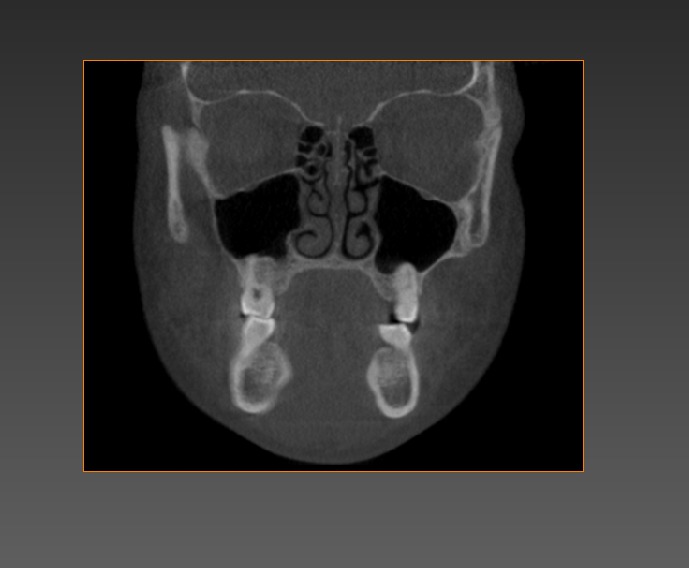

Objectives: The purpose of this study was to analyze maxillary sinus changes over time in adolescents, in terms of shape and volume, using cone-beam computed tomography – CBCT reconstructions.

Methods: A total of 274 maxillary sinus in 137 CBCT scans of 57 patients were analyzed. For each patient, there was a time lapse of either 2, 3 or 4 years between examinations. All images were from an available pool of scans of patients from the University of Alberta Orthodontic Clinic. CBCTs were visualized and evaluated using AVIZO®. The outline of the sinuses was landmarked manually in its entirety. 3D models of the air-filled structures were constructed and the shapes and volume of each sinus was evaluated. Ten images of scans not included in the study were analyzed to determine intra-reliability of each the overall shape and volume of each sinus. ANOVA, Bonferroni correction and t-test were used to compare groups.

Results: It was found that 88.3% of the obtained datasets are most similar to another dataset obtained from the same patient showing the method of measurement as being reliable. The changes in shape of the maxillary sinuses were subtle and minimal, at a value of 5.13mm (SD 5.58mm). The changes in volume were substantial from time 1 to time 2 (and to time 3 when applicable); the percentage of change was of 21.3% (SD 23.79%).

Conclusions: Maxillary sinus volume grows considerably over time, while its shape only changes subtly. In adolescents, the sinuses change substantially as a whole and the modifications are significant, as shown by the CBCT images and landmarks.